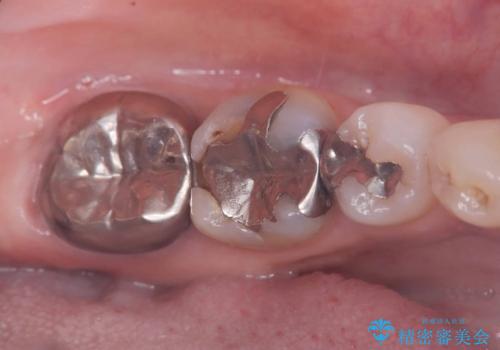

- 銀歯の下の虫歯です。お写真で分かるように広範囲で深い虫歯でした。

1歯はオールセラミッククラウンもう1歯はセラミックインレーで治療を行いました。